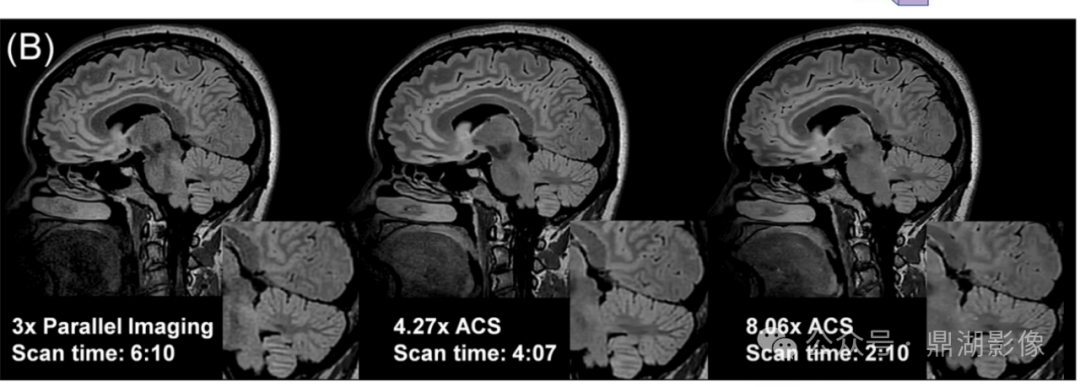

(A)运动伪影实时矫正开启前后的弥散加权图像与方向编码彩色图谱对比,以及(B)ACS加速成像的示例。

与传统的并行成像(parallel imaging)参考图相比,来自ACS的图像实现了相近的图像质量,以及更快的成像速度。